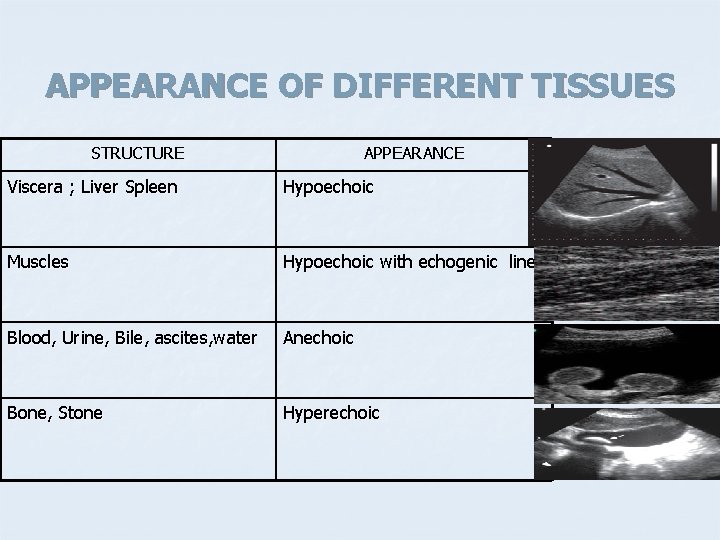

B MODE COLOURS BLACK ANECHOIC GREY HYPOECHOIC WHITE ECHOGENIC

APPEARANCE OF DIFFERENT TISSUES STRUCTURE APPEARANCE Viscera ; Liver Spleen Hypoechoic Muscles Hypoechoic with echogenic lines Blood, Urine, Bile, ascites, water Anechoic Bone, Stone Hyperechoic